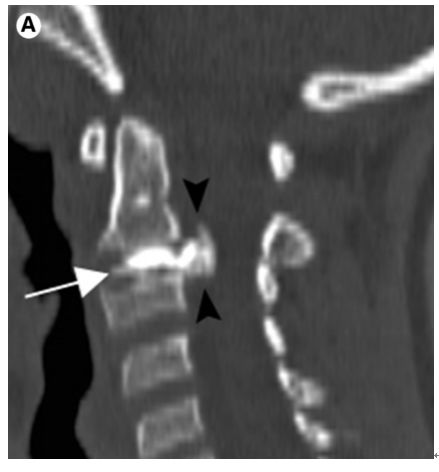

明确诊断主要通过影像学方法,颈椎CT是关键。颈长肌钙化性肌腱炎特异性的影像表现是C1-4椎体前缘软组织肿胀和积液与C1椎体前弓下方不规则钙化沉着共存。

图:C1椎体前弓下方不规则钙化沉着

图:椎前积液

图:椎前积液和C1椎体前弓下方不规则钙化沉着

图:椎前软组织肿胀

颈椎侧位片能够显示上颈椎前纵韧带和颈长肌组成的软组织影增宽,密度增高,正常时宽度为3-4mm,急性炎性水肿时可增宽到1cm以上,并可显示椎前软组织内的钙化影,一般位于C1-2水平。此外,还可见颈肌痉挛引起的颈椎前凸消失。颈椎侧位平片所见的发育性寰椎前弓的下方附属小骨片、寰椎前弓的撕脱骨折以及茎突舌骨肌韧带的钙化极易与本病所见的钙化混淆。

CT的高分辨率能够明确肌腱内的钙化,能够明确是钙化而不是其他骨骼来源的高密度影。钙化一般位于寰椎前弓的下方和枢椎齿状突的前方,少部分可位于下颈椎前侧。CT有助于明确椎体前积液的存在和排除其他病理表现,如骨折或脓肿。MRI对诊断不是必须,但有时可帮助确定软组织异常,排除咽后脓肿,脊椎炎或肿瘤。MRI检查T2加权在椎前可见局限性的裂隙样区域,大多位于C1-4水平,呈高信号改变,这反应是由于炎症引起的积液。T2加权、脂肪抑制序列和T1加权对鉴别积液和脂肪组织、含脂肪的骨髓以及咽后感染、脊椎炎有重要作用。MRI检查在钙化检查方面存在不足,T2加权呈低信号。

36岁女性,急性颈痛、吞咽困难伴颈部僵硬,MRI示C1-2前部颈长肌增厚呈低信号,提示钙化(长箭头)和C1-4椎前积液(无线箭头),经类固醇和止痛药治疗8天后症状消失,复查MRI提示上述表现消失。(PMID: 18765656)

C1-2前侧低信号(无线箭头)和C1-5椎前水肿(长箭头) (PMID: 19567634)

40岁男性,低热伴急性颈痛、张口困难1天,颈椎CT提示椎前钙化(箭头),经洛索洛芬60mg,每日三次,连续五天治疗,3天后症状改善,3月复查CT钙化消失。(PMID: 25918175)

32岁男性,颈肩部疼痛1月,喝水时轻度吞咽困难伴颈椎活动受限,无发热,化验指标正常,经非甾体抗炎药和秋水仙碱治疗后症状改善,4月后复查颈椎侧位片(D,E)钙化消失。(PMID: 25941110)

30岁女性,诊断为颈长肌钙化性肌腱炎,但钙化位于不寻常的位置:C4-5椎间隙前侧。A:颈椎侧位片示寰枢椎半脱位(长箭头)和椎前软组织肿胀(无线箭头);B,C和D:颈椎MRI示C1-6椎前软组织肿胀伴积液,D示齿状突骨侵蚀(无线箭头)

上述病人,E为增强,F为抑制像,G和H:经非甾体抗炎药治疗3天后查颈椎CT示C4-5椎前无定形钙化。

上述病人,I和J: 入院4天后复查颈椎MRI示椎前积液明显减少; K,随访2个月复查CT示C4-5前钙化灶减小。(PMID: 21852912)